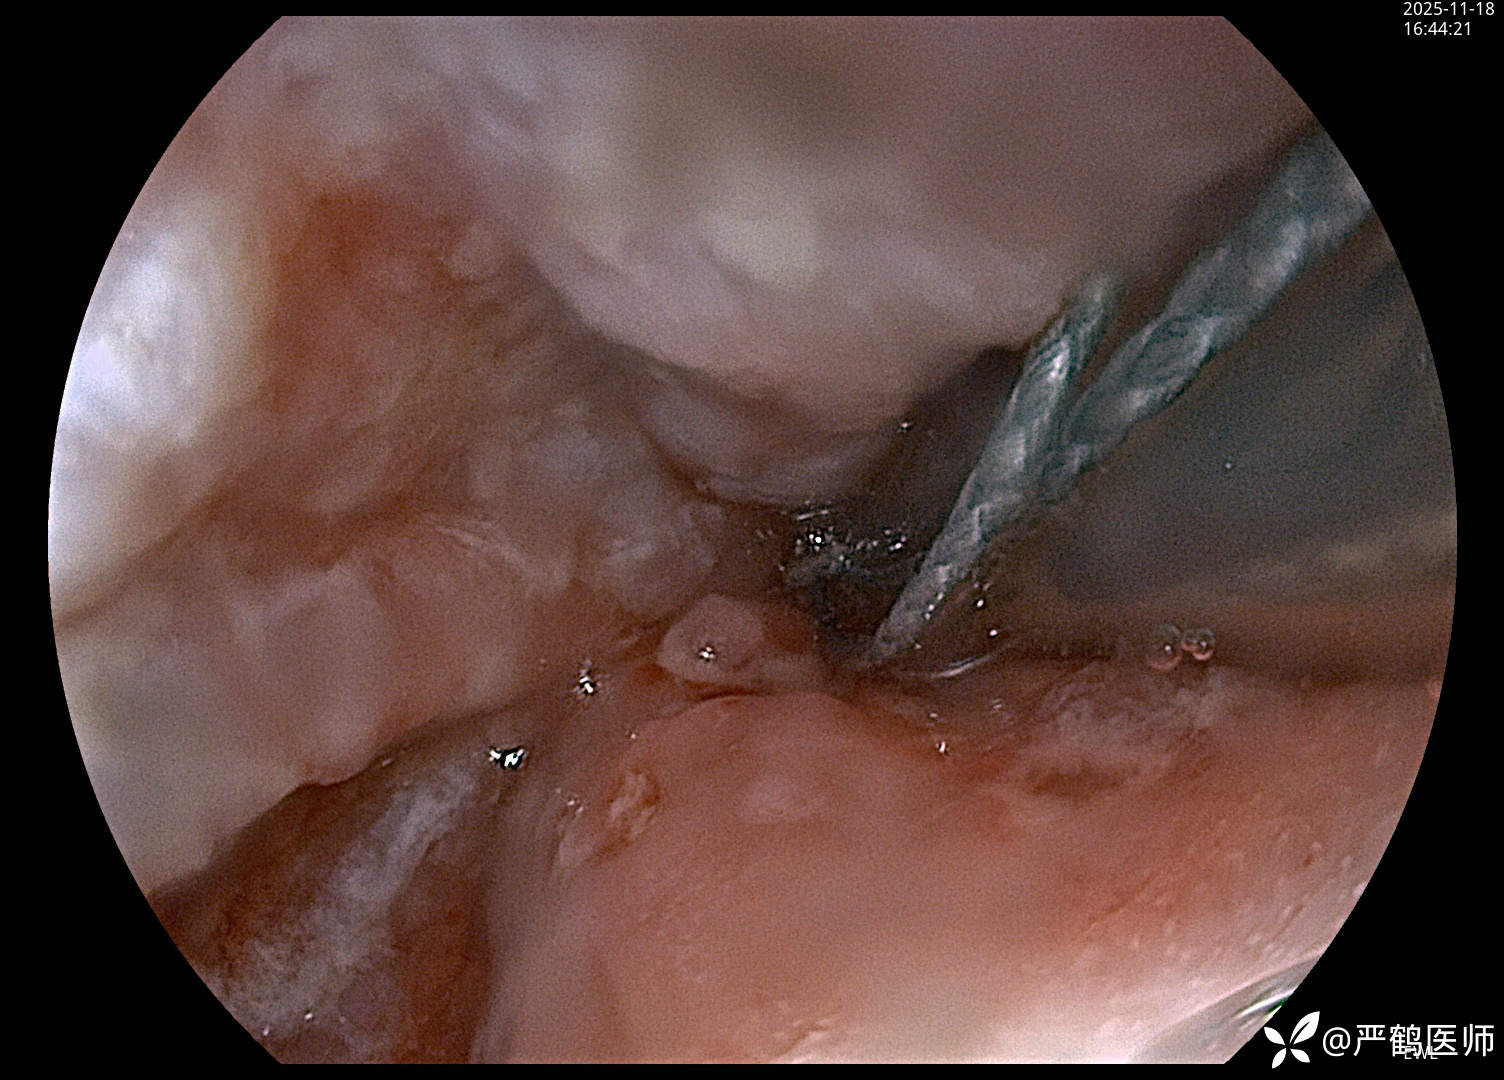

食管癌覆膜支架置入术

老年男性,食管距门齿30cm处肿瘤至进食梗阻,无法手术,家属不愿进一步行放化疗治疗,置入全覆膜食管支架解除梗阻,缓解进食困难症状